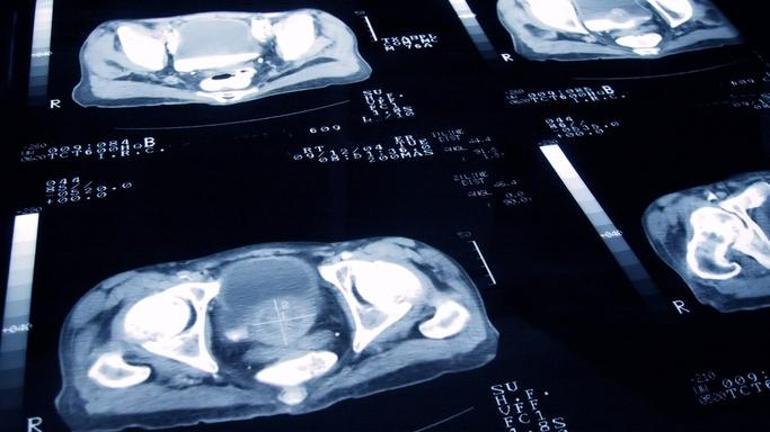

Erkeklerde en yaygın kanser türü olan prostat kanserinde erken tanı artık çok daha mümkün olmuştur. Yakın zamanda geliştirilen teşhis yöntemleri sayesinde, hastalık semptomların ortaya çıkması olmadan teşhis edilebilir. Bu, işleme sürecindeki başarı oranını arttırır. Sinsi olan prostat kanseri, herhangi bir semptom olmadan uzun süre gelişebilir. Bununla birlikte, gelişmekte olan MR teknolojisi sayesinde, tümör daha önce fark edilebilir.

Yeni gelişmiş tanı yöntemleri klasik biyopsi uygulamalarının yerini alır. Şimdi, şüpheli bölgeye odaklanarak, sivri bir atışla tanımlanmış bir teşhis yapmak mümkündür.

“Prostat kanseri çok sinsi bir hastalıktır, çünkü ilerleme sırasında herhangi bir semptom sağlamaz. Bununla birlikte, ayrıntılı görüntüleme sağlayan MR teknolojileri sayesinde, şimdi prostat kanserini daha net görebiliriz, ilk aşamayı teşhis edebiliriz. Bu, tedaviye daha önce başlamamıza izin verir.

Geçmişte, şüpheli bir durum olduğunda rastgele alanlardan örnekler alıyorduk. Yürüyüş alanını bir turuncu bulma girişimi olarak düşünebiliriz. Bununla birlikte, manyetik rezonans görüntüleme sayesinde, şüpheli bölge doğrudan tespit edilir ve sadece o bölgede biyopsi ile teşhis edilir.

Klasik yöntemlerden farklı olarak, tüm prostat bezine değil, sadece tümör bölgesine müdahale ediyoruz. Bu şekilde, ikimiz de tanıyı daha önce koyduk ve hastaya daha rahat ve etkili bir tedavi sunuyoruz. “